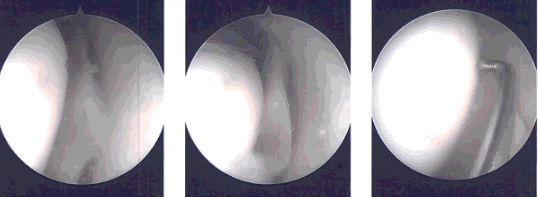

Imágenes intraoperatorias

Se realizó un portal de acceso médico utilizando una aguja espinal. El examen del compartimento medial mostró una compleja ruptura del cuerno posterior del menisco medial. El desgarro estaba desbordado. El menisco medial se desbridó con el uso de mordidor recto, mordidor superior y afeitador.

El examen de la muesca intercondilar mostró LCA intacto con degeneración. El examen del compartimento lateral mostró márgenes mediales deshilachados del menisco lateral, que se desbridó con el uso de la mordedora ascendente y la afeitadora.

Se realizó el desbridamiento de la articulación patelofemoral y la condroplastia se realizó mediante el uso de la varita térmica y la afeitadora. La plica suprapatelariana era permanente y se extirpó con el uso de una varilla térmica.

El endoscopio se introdujo por la puerta medial y los instrumentos se introdujeron por la puerta lateral para completar la meniscectomía medial.